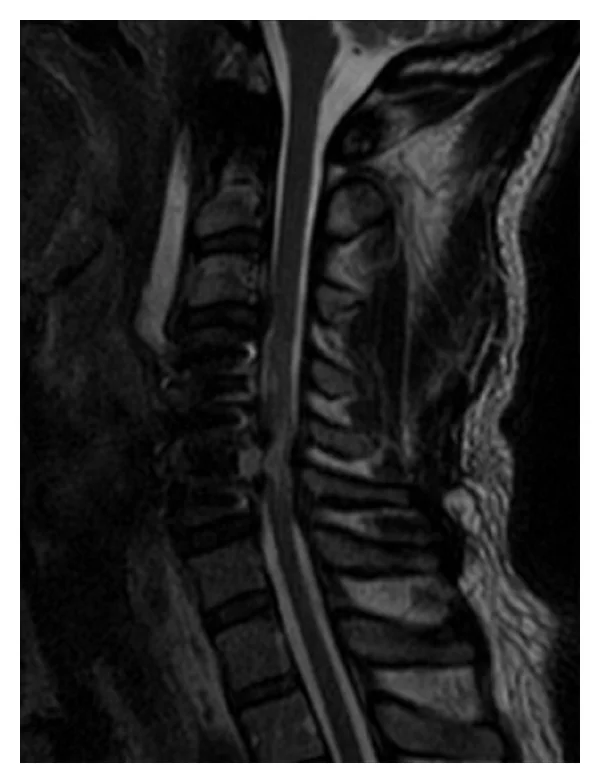

At day 3 a postoperative MRI demonstrated a large area of high signal changes on T2-weighted MRI intrinsic to the cord (“white cord syndrome”) but no residual compression (Figure 4). Following intravenous administration of gadopentetate dimeglumine contrast at MRI postoperatively there was no pathologic enhancement of the spinal cord lesion, and therefore the hyperintense changes involving the cervical spine at the C5 level were considered consistent with spinal cord edema (Figure 3). When compared to the preoperative MRI, it was clearly present but partially masked by the large herniated disc. Day 2 postoperatively the patient was returned to the operating room to investigate any SSEP changes to and to see if there was continued recovery. There were no changes to SSEP compared with intraoperatively. The decision was then made to continue steroids and follow the patient clinically with serial MRIs. Within two days the patient moved both upper limbs and had 3/5 power in the toes.

Figure 4: Day 3 postoperative MRI demonstrates more clearly the spinal cord edema intrinsic to the cord—a “white cord syndrome.”

Figure 6: Sagittal T2-weighted MRI at the latest 16-month followup showing a persistent “white cord syndrome.”

In this patient, a massive herniated disc seemed to have compressed the cord chronically and produced a large area of cord edema, but the patient had compensated. Over time his radiculomyelopathic symptoms progressed and he sought surgical treatment. The acute decompression of the herniated disc resulted in immediate cord expansion within the open canal space, and the compressed segment of the cord exposed to a rush in blood supply. We postulate that this sudden cord expansion and reperfusion may have lead to disruption in the blood brain barrier (BBB), or in the blood spinal cord barrier, and triggered a cascade of reperfusion injury resulting in acute neurologic dysfunction at and below the C6 level. The MRI appearance on sagittal T2-weighted MRI and the clinical results of incomplete paralysis without a clear understanding of the pathophysiology of this condition led us to use the term “white cord syndrome.”

In our case described herewith, MRI performed at day 1 postoperatively demonstrated gliosis. However, there remains much debate about the clinical relevance of high signal intensity on the T2-weighted MR images. The debate extends to the reversibility of the spinal cord edema also [27]. It should be noted that the increased T2-weighted signal intensity was present even before the decompression, so demyelination may also be a possibility in this patient. We highlight these factors simply to reflect on the different possible reasons for the edema and the increased signal intensity.